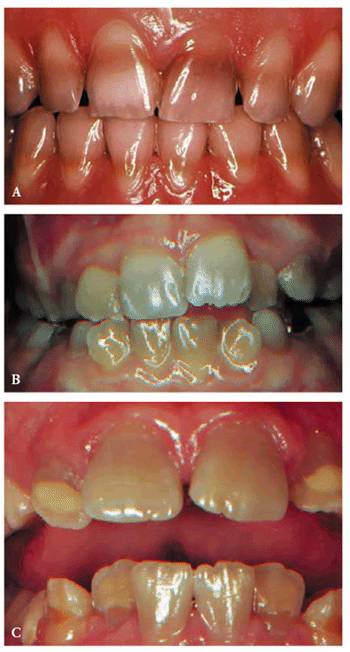

detecting color shifts in a crown (Figures 19-1A, and 19-1B). A tooth with a pink or reddish

hue would more than likely indicate internal hemorrhage from a recent injury (Figure 19-2), a dental procedure (Figure 19-3), or gingival tissue hyperplasia

that has invaded a coronal cavity produced by caries or resorption (Figures 19-4A 19-4B 19-4C, and 19-4D).

A gray, blue, or black color might indicate blood infiltrate hemostasis within

the dentinal tubules and chamber, long-term necrotic tissue (Figure 19-5), or silver precipitants from

certain root canal sealers and filling materials (Figures 19-6A 19-6B, and 19-6C). A yellow or brown (Figures 19-7A, and 19-7B) unrestored crown often represents

a physiologically calcified nonpathologic obliteration of the root chamber/

canal. Pharmacologically affected (ie, tetracycline-stained) teeth may vary in

color from yellow to black (Figures 19-8A to

C), and

their drug fluorescence and etiology may be verified by using an ultraviolet or

Woods black light.

Figure 19-1A: Transillumination of a maxillary left central incisor with a necrotic pulp.

Figure 19-1B: Transillumination of the adjacent tooth with a vital pulp. Because there is active blood flow through the live pulp tissue, the tooth appears brighter to the fiber-optic light than the adjacent tooth with a necrotic pulp.

Figure 19-2: The maxillary central and lateral incisor teeth experienced a concussion injury and there was subsequent extravasation of blood causing the reddish hue.

Figure 19-3: One week following crown preparation, the tooth structure was red, signifying extravasation of blood and the need for pulp extirpation.

Figure 19-4A: Pink spot as a result of external resorption.

Figure 19-4B: Radiograph of the same tooth showing external resorption.

Figure 19-4C: Pink spot as a result of internal resorption.

Figure 19-4D: Radiograph of the same tooth showing internal resorption.

Figure 19-5: Discolored maxillary central incisors with necrotic pulps.

Figure 19-6A: Discoloration from silver-containing root canal cement.

Figure 19-6B: Gray color of crown from a post.

Figure 19-6C: Same radiograph as 19-6B. An unnecessary post that caused the discoloration.

Figure 19-7A: The crown of this maxillary central incisor discolored gradually over a 3-year period following a concussion injury. The complete fill-in of the pulp chamber with dentin is the cause of the yellowish brown hue. In the absence of periapical radiographic changes and clinical symptoms, endodontic therapy is not indicated.

Figure 19-7B: Radiograph of a similar maxillary central incisor 10 years after a concussion injury. The pulp chamber is filled in with dentin producing the discoloration. In this case, there was pulp death years after the discoloration appeared. Because the pulp canal was obliterated, a surgical approach was used to seal the apex.

Figure 19-8A to C: (A) Brown staining from Terramycin. (B) Gray staining from Acromycin. (C) Tan staining from Aureomycin.